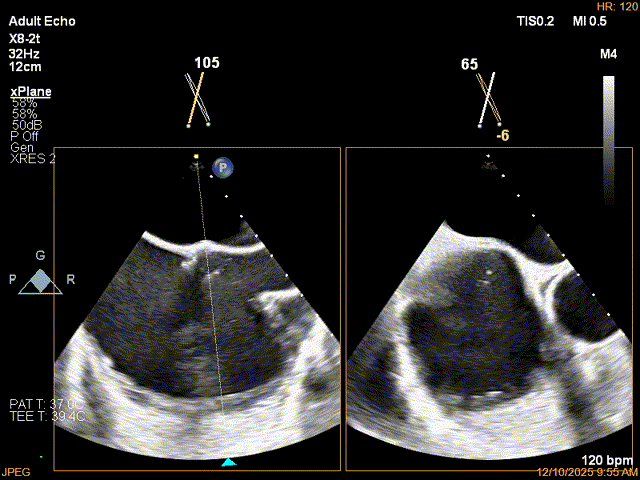

全麻下穿刺右股静脉,在TEE指导下完成房间隔穿刺,穿刺处与二尖瓣环距离5.3cm。将Superstiff导丝送至左房,应用18F鞘管扩张穿刺部位,沿导丝将可操纵导引导管送入左房。

房间隔穿刺高度5.3cm

穿刺位点3点钟方向